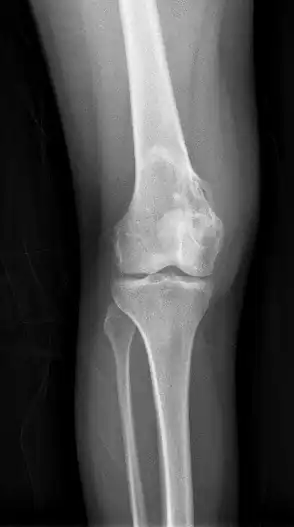

Chondrosarcoma long bone of thigh near knee

Imaging studies - including radiographs ("x-rays"), computerized tomography (CT), and magnetic resonance imaging (MRI) - are often used to make a presumptive diagnosis of chondrosarcoma.[11] However, a definitive diagnosis depends on the identification of malignant cancer cells producing cartilage in a biopsy specimen that has been examined by a pathologist. In a few cases, usually of highly anaplastic tumors, immunohistochemistry (IHC) is required.

There are no blood tests currently available to enable an oncologist to render a diagnosis of chondrosarcoma. The most characteristic imaging findings are usually obtained with CT.

Imaging